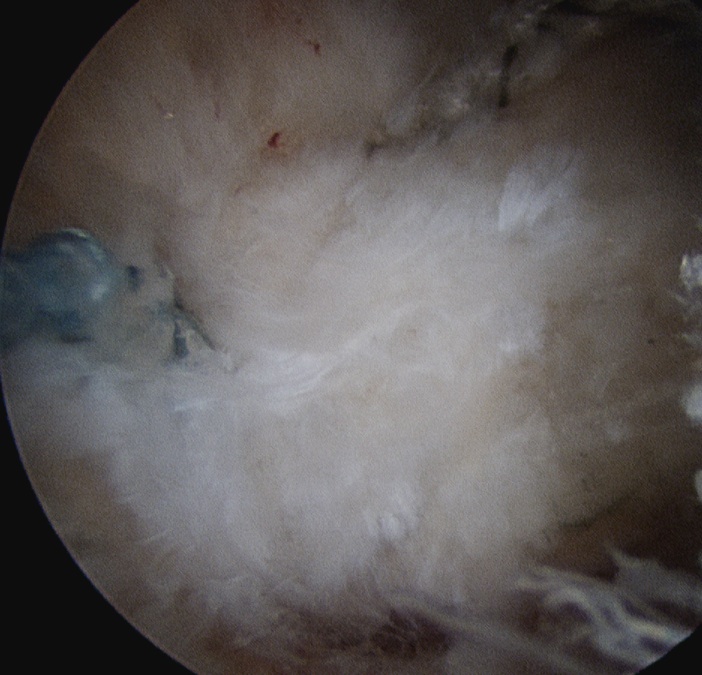

Calcium IncisionCalcium in TendonCalcific Tendonitis Arthroscopy 4

Longitudinal incision of rotator cuff / debridement of calcium / rotator cuff repair